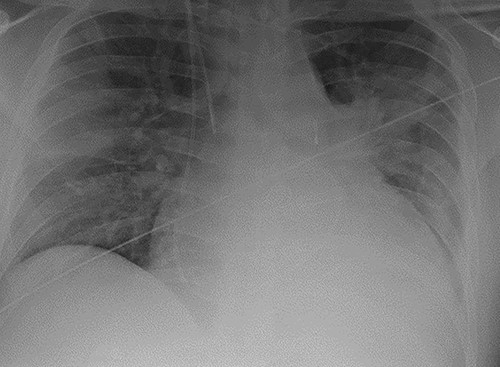

As part of his work-up for cardiac transplantation he was found to be a carrier of the HbS sickle cell trait, with an estimated HbS concentration of 34.4%. Due to his deteriorating condition and the uncertainty as to his candidacy for transplantation [5], the management plan was for mechanical circulatory support as a bridge-to-decision. An axillary IABP was inserted as previously described [6]. Unfortunately, he continued to deteriorate, requiring the implantation of a short-term BiVAD, as previously described [7]. His overall condition improved with BiVAD support—there was recovery of renal and liver function and resolution of pulmonary oedema, as shown in Fig. 2. However, there was no evidence of myocardial recovery, and he was therefore placed on the super-urgent heart transplant waiting list.

Chest radiograph demonstrating biventricular assist device pipes in situ and resolution of previous pulmonary oedema.